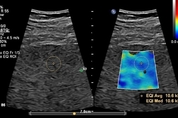

㈜필립스코리아는 한층 기능이 강화된 초음파 제품 포트폴리오를 공개했다. 이번 업그레이드는 범용부터 고사양장비까지 적용돼 다양한 임상 영역에서 활용성을 높이고 의료진의 워크플로우를 지원하는 다양한 기능을 제공한다. 최근 비만과 당뇨병 등 대사질환이 늘어나면서 간 질환과 심혈관 질환이 동시에 나타나는 환자가 빠르게 증가하고 있다. 실제로 국내 성인 비만율은 2022년 기준 37.2% 수준으로 상승세를 이어가고 있으며 지방간 유병률은 성인 인구의 20~30%에 이른다. 이와 함께 19세 이상 성인의 고혈압 유병률은 약 22%, 당뇨병은 약 10%에 달해 심뇌혈관질환 위험도 커지고 있다. 지방간은 간암으로, 고혈압과 고지혈증은 심근경색과 뇌졸중으로 이어질 수 있어 조기 진단의 필요성이 갈수록 커지고 있다. 이러한 배경 속에서 MR, CT, X-ray 등 다양한 영상진단 장비가 활용되고 있으며 특히 방사선 노출 위험이 없어 반복 검사가 가능한 초음파는 간과 심장을 포함한 주요 장기 진단에 적합한 대안 중 하나로 주목받고 있다. 더 나아가 최근에는 AI 기반 자동화 기술이 접목되면서 초음파 검사의 재현성과 효율성이 크게 향상되고 있다. 이러한 상황에서 필립스는 한층 기